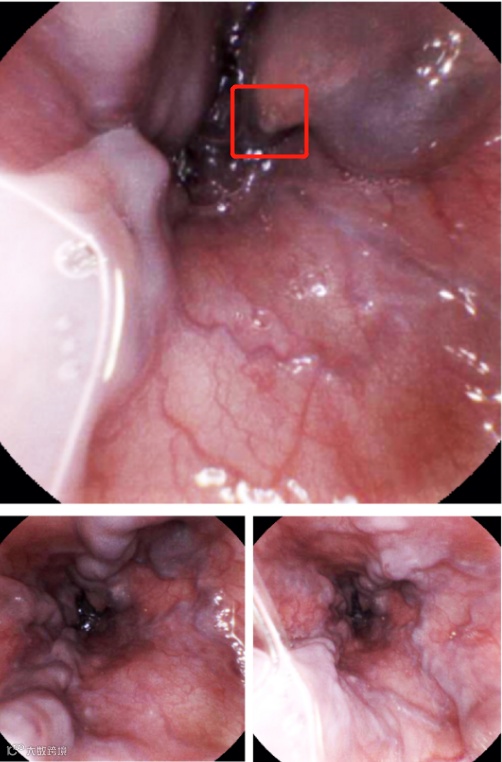

牵线胶囊检查

可分离式牵线磁控胶囊胃镜检查结果显示,李爷爷食管与胃静脉曲张严重,食管的中下段一处破裂出血。

术后复查依然采用可分离式牵线磁控胶囊胃镜,结果显示李爷爷术后恢复良好。

术后复查